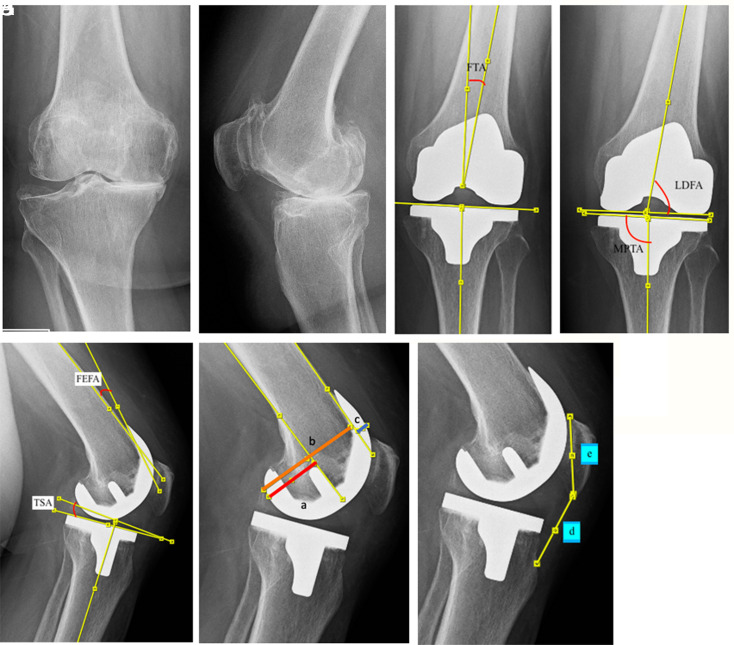

Objective: The aim of this study is to compare the clinical and functional results of single-radius (SR) and multi-radius (MR) femoral components in total knee arthroplasty (TKA). Methods: A total of 74 patients who underwent TKA surgery by a single surgeon between 2018 and 2021 were included in the study. The patients were then divided into 2 groups according to their femoral component design: group SR (38 patients) and group MR (36 patients). Except for gender and follow-up duration (P < .05), no significant difference was observed in age, American Society of Anesthesiologists scores, and BMI (P > .05). Knee range of motion, visual analogue scale (VAS), and combined KSS (Knee Society Score) were evaluated at the preoperative and final controls of the patients. In addition, frequency of anterior knee pain (AKP), AKP scale, Western Ontario and McMaster Universities Osteoarthritis Index (WOMAC), Hospital for Special Surgery (HSS) score, and the Forgotten Joint Score-12 (FJS12) were evaluated at the final follow-up. Results: There was no difference between the 2 groups in terms of postoperative range of motion (ROM), VAS, combined KSS, and HSS (P > .05). The frequency of AKP in patients with SR was found to be statistically lower than those with MR (P=.021; P < .05). The AKP scale was found to be statistically significantly lower in patients with prosthetic type MR compared to patients with SR (P=.04; P < .05). Singleradius patients had significantly better FJS-12 (P=.014; P < .05) and WOMAC scores (P=.003; P < .05). Conclusion: The results of this research showed that good clinical and functional results are obtained with TKA regardless of the femoral component design. Single-radius prostheses show better results than MR prostheses in terms of the frequency and severity of AKP. While there is no difference between femoral designs in terms of TKA-specific functional results such as KSS and HSS, the WOMAC score, which measures disease-related functions, provides better clinical results in SR designs. Additionally, SR designs show significantly better results in functional scores indicating patient satisfaction, such as FJS-12.